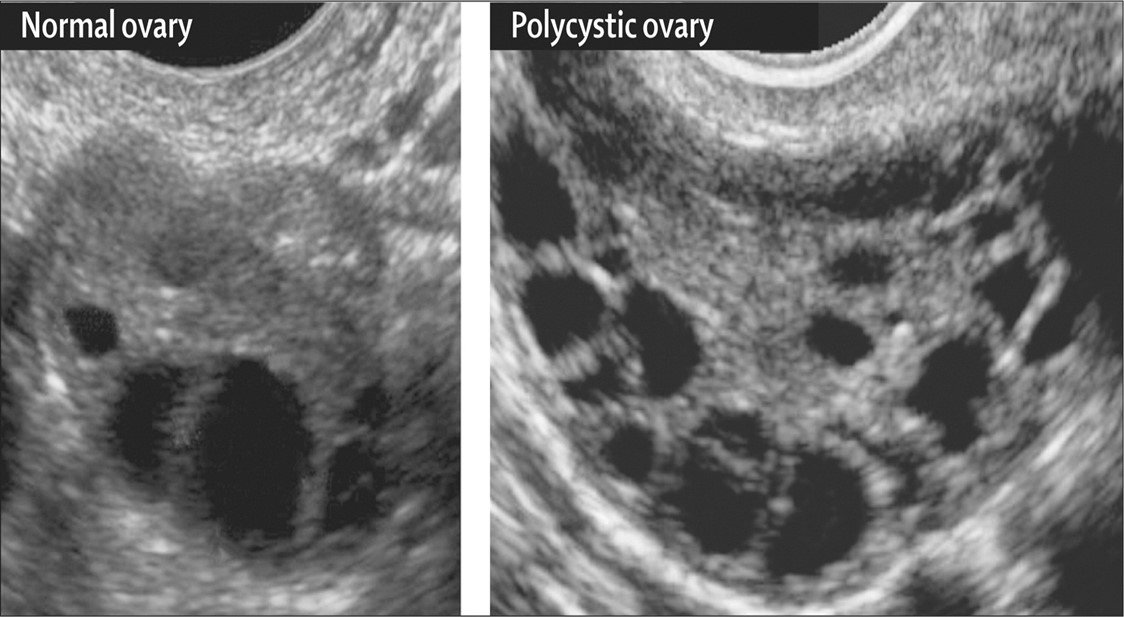

3- شکل تخمدان در سونوگرافی ( به صورت تخمدانهای پلی کیستیک با تعداد مشخصی فولیکول)